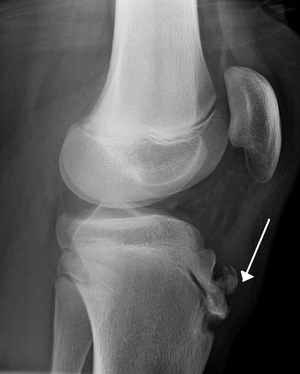

Osgood-Schlatter disease

- Apophysitis of tibial tubercle resulting from repeated normal stresses or overuse

- If obtained shows nonspecific irregularities of tibial tubercle

- If initial presentation includes swelling, inability to actively extent the knee, decreased strength with knee extension, or inability to walk, obtain radiograph to evaluate for avulsion fracture of the tibial epiphysis